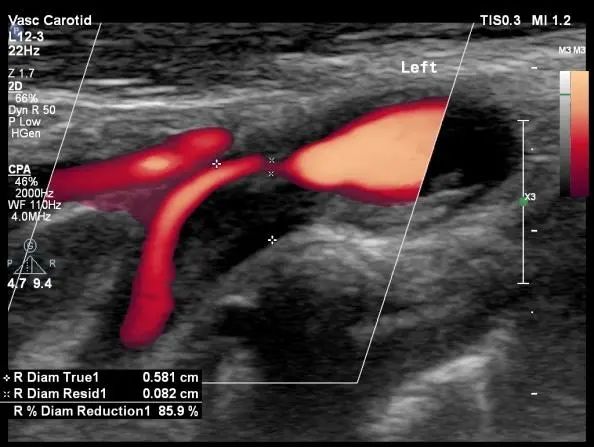

“健康”体检者。颈动脉超声提示颈动脉重度狭窄。TCD提示颅内侧支循环代偿充分。无创的头颈血管超声的一体化评估是筛查脑血管病高危人群的首选,是“前哨兵”。